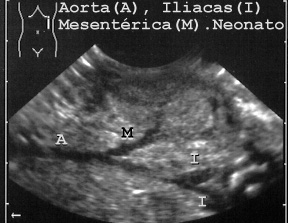

La vena yugular también es visible sin obstrucción o con algo en su interior. En los neonatos los vasos se ven con facilidad (Fig 29).

29AORTAN.JPG (27611 bytes)

Fig 29